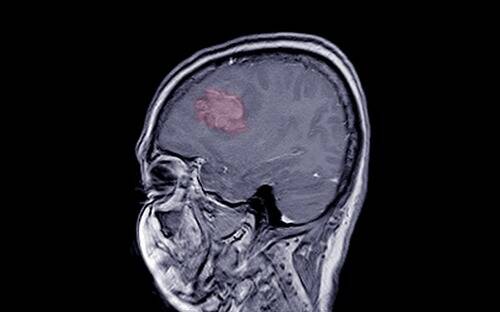

Meningiomas are tumors that develop in the meninges, the layers of tissue covering the brain and spinal cord. These tumors can vary in size and severity, with some growing slowly and others presenting serious risks.

Tumor Location

Meningiomas can form in various parts of the brain and spinal cord, with common locations being the skull base, near the brain, and spinal cord. Tumors in these areas can cause different symptoms depending on their location and size, such as headaches, vision problems, or seizures.

Symptoms of Meningiomas

The symptoms of meningiomas vary based on the tumor’s size, location, and grade. Common symptoms include persistent headaches, vision changes, seizures, and neurological deficits. If left untreated, some meningiomas can grow large enough to compress nearby brain tissue or organs, causing life-threatening complications.

Diagnosis and Treatment

Meningiomas are typically diagnosed using imaging techniques such as MRI or CT scans. Treatment options depend on the tumor’s size, location, and grade. Surgery, radiation therapy, and in some cases, chemotherapy, are common treatment approaches. The prognosis is often favorable for benign meningiomas, but more aggressive treatment may be necessary for higher-grade tumors.